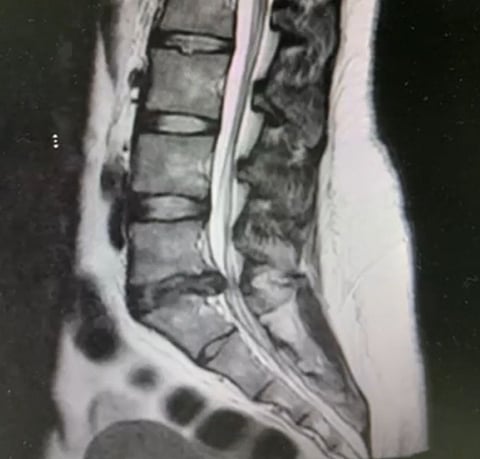

وبعد إجراء الفحوصات اللازمة، تبيّن وجود انزلاق غضروفي بين الفقرة القَطنية الخامسة والعَجُزية الأولى.

وقرر الفريق الطبي إجراء عملية جراحية بعد أن فشلت المسكنات والعلاج الطبيعي في النتائج المرجوة في تخفيف الألم، وبعد تنويم المريضة أُجريت لها عملية إزالة الغضروف الضاغط على الأعصاب باستخدام تقنية التدخل المحدود بالمنظار، عبر فتحة جراحية صغيرة لا تتجاوز 2 سم، وخرجت المريضة من المستشفى بعد يوم واحد من العملية وهي في حالة صحية جيدة.